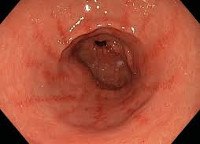

Следующим этапом диагностики является консультация врача-эндоскописта. Наиболее точным методом диагностики поверхностного гастродуоденита служит эзофагогастродуоденоскопия с эндоскопической биопсией и морфологическим исследованием биоптатов. Во время эндоскопии визуально выявляется гиперемия (катар) слизистой, утолщение и отек складок пилорического отдела желудка и двенадцатиперстной кишки.